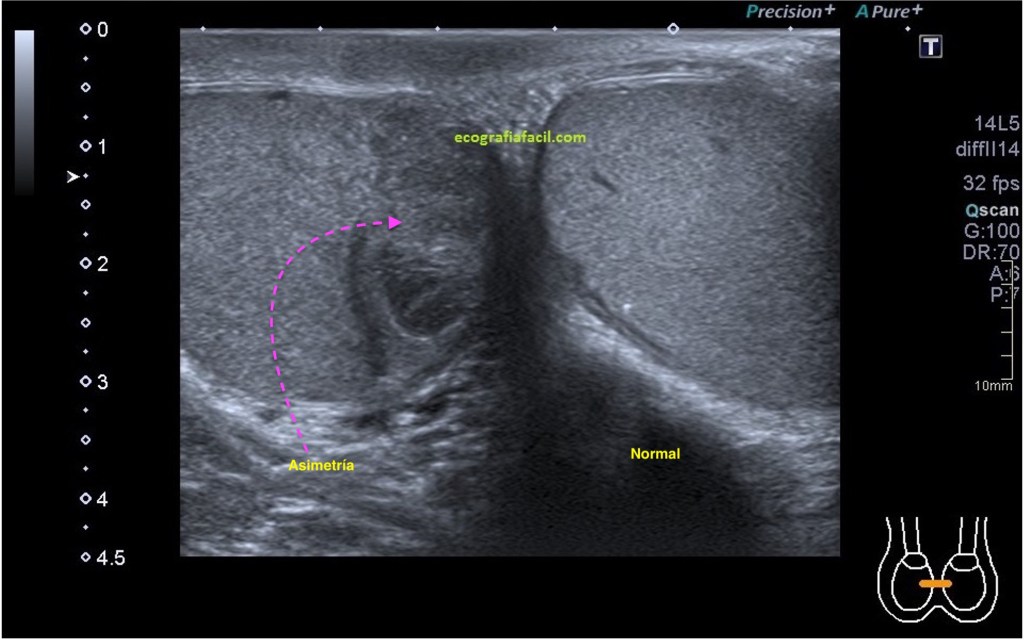

En la ecografía pediátrica, por ejemplo, en la ecografía transfontanelar, es vital, la hoz interhemisférica divide al cerebro del neonato en dos estructuras simétricas, simplemente la comparativa en tiempo real de ambos hemisferios ya nos ofrece una información de altísimo valor, al punto que aunque no seamos capaces de ver que patología está afectando a ese órgano, la asímetría es indicador de que «algo pasa», la imagen que te muestro a continuación es muy clarificadora. Paciente de un mes de vida, controles de salud normales, se le pide ecografía «de control» y observo esta imagen:

Me llama la atención una leve alteración en la ecogenicidad del cerebro derecho con respecto al izquierdo, es ligeramente más hiperecogénico…no tiene importancia aquí el diagnóstico, quiero que se entienda la importancia de que una buena técnica, un buen ajuste de los parámetros y el reconocimento de la simetría fue vital para el diagnóstico.